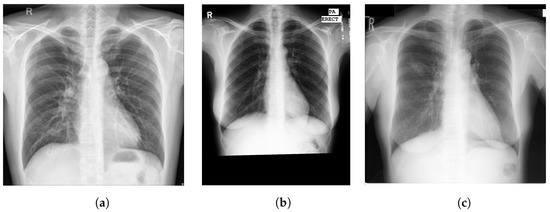

2. Materials

The primary databases used to train and test our proposed system were formulated from three publicly available datasets that are widely used in CADe and CADx systems that detect and diagnose pulmonary diseases. The databases were the Shenzhen chest X-ray set [34], Montgomery County (MC) chest X-ray set [34], and Japanese Society of Radiological Technology (JSRT) database [35]. Figure 1 shows examples from each database. A 400-image partition of the Shenzhen dataset was used to train the individual lung segmentation networks. The selector network was trained using the remaining 166 images in the Shenzhen dataset. The other two datasets were used exclusively for testing the final segmentation performance and for testing the TB detection network. The CRs in all three datasets were zero-padded symmetrically as needed to create a square aspect ratio and then resized through bicubic interpolation to 256 × 256 to match the input layers of the lung segmentation networks.

Figure 1. Example CRs from three databases: (a) radiograph from the Shenzhen database [34], (b) radiograph from the MC database [34], (c) radiograph from the JSRT database [35].